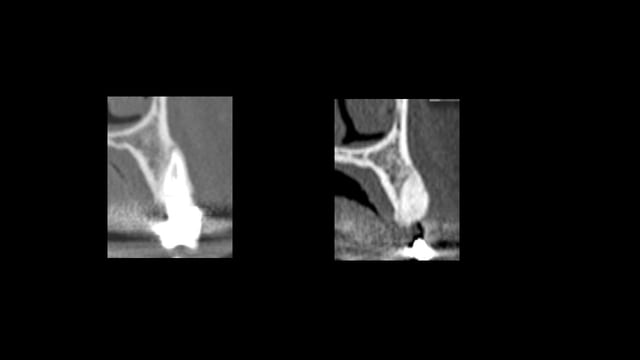

Scanner de contrôle quelques mois plus tard...

Preservation de crete - Eugenol

la procédure a permis de conserver le volume osseux disponible voir même l'augmenter, la difficulté est que le produit de comblement est radio-opaque et que sa cohésion est délicate à aprécier. peut -tu faire part de tes sensations lors du forage.